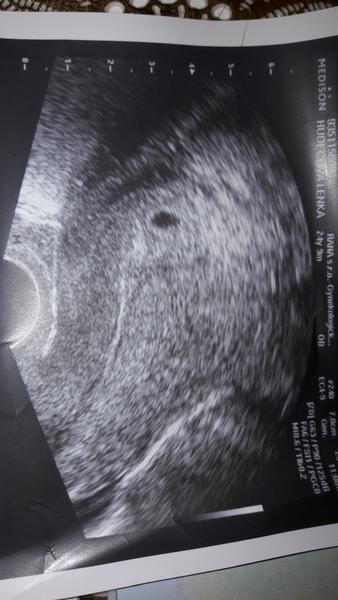

@laydy7777 moj dr to ma takto 🙂

@lenakiss vsak aj tam je to krasne vidno. Super gratulujem.